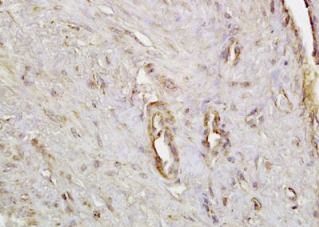

组织/细胞:人子宫内膜组织;4%多聚甲醛固定石蜡包埋;

抗原提取:柠檬酸缓冲液(0.01M,pH 6),15min煮沸,用3%过氧化氢阻断内源性过氧化物酶30min;37℃下阻断缓冲液(正常山羊血清)20 min;

孵育:抗肌动蛋白α/αSMA多克隆抗体,未结合 1:200,在4°C下过夜,然后与二级抗体结合,DAB染色。